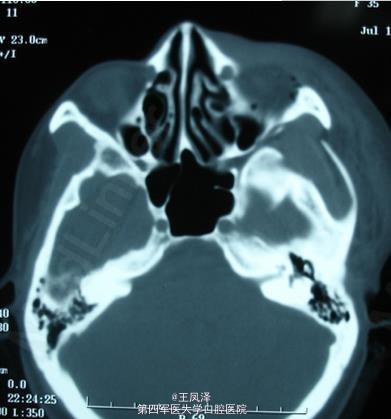

颧骨-眶底骨折病历

患者,女,25岁,车祸后送诊

双侧上颌骨骨折、左颧骨骨折

眶底骨折缺损重建